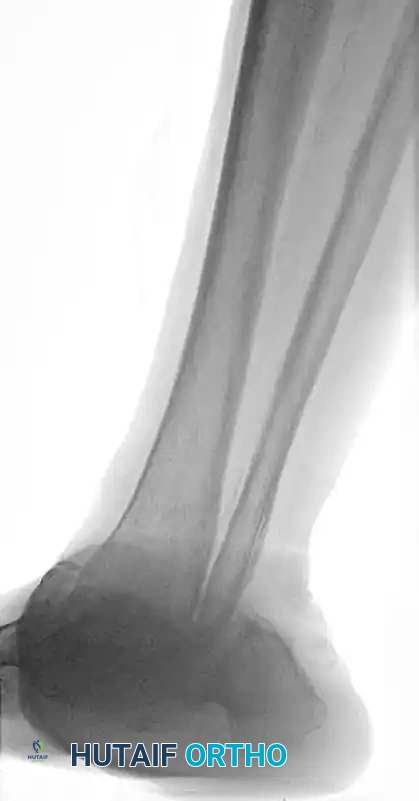

The following preoperative and postoperative radiographs demonstrate the successful application of augmented fixation in a young diabetic patient with a severe bimalleolar fracture-subluxation:

FIGURE 85-25 A and B: Preoperative radiographs of a highly unstable bimalleolar ankle fracture-subluxation in a 19-year-old man with a 12-year history of insulin-dependent diabetes mellitus.